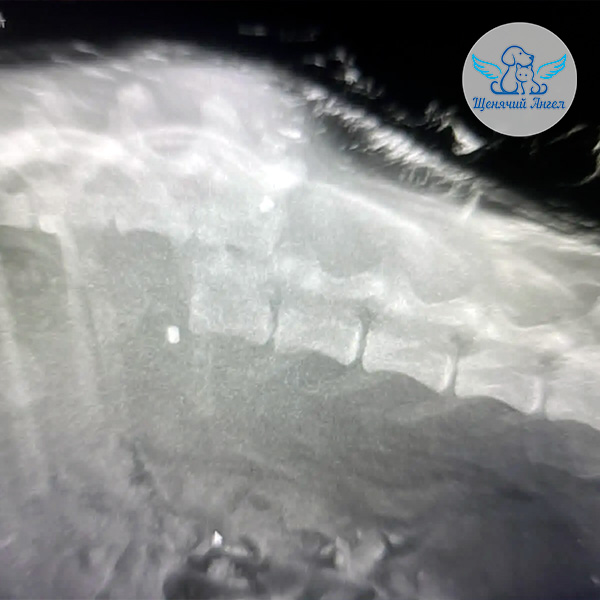

🩻 Рентген подтвердил застарелый перелом позвоночного столба со значительным смещением.

Также у Хрома обнаружены инородные предметы – пули: одна в зоне перелома позвоночника, другая в мягких тканях подколенной области 😔

К сожалению, прогноз в отношении восстановления опороспособности и самостоятельного мочеиспускания неблагоприятный. Но, несмотря на тяжесть диагноза, Хрому показано хирургическое лечение – стабилизация позвоночника ☝🏻. Операция необходима, чтобы устранить патологическую подвижность в месте перелома, уменьшить болевой синдром и дать ему возможность жить без постоянных мучений.